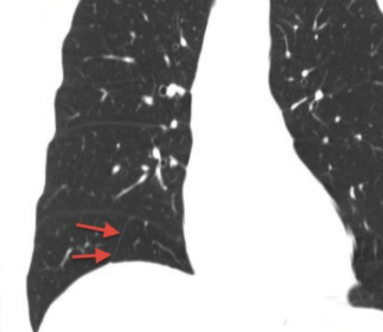

Scissure Inférieure Accessoire

- 12% des patients

- A Droite++

- Sépare le segment médio-basal du reste